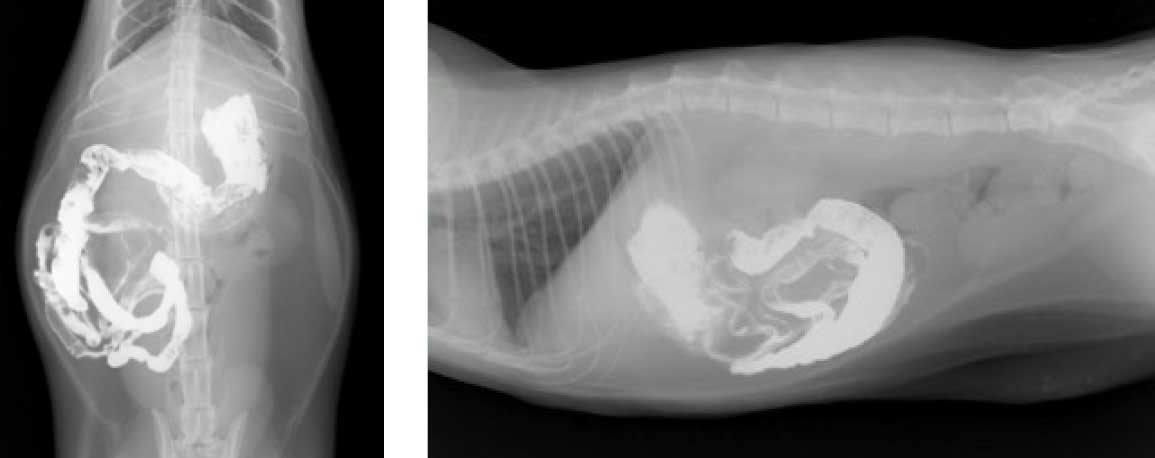

造影X線検査

バリウムなどの造影剤を使用して、異物や構造的異常の有無、また、消化管運動の停滞などを評価します。

胃内異物

特に若齢の犬に認められることが多く、異物による胃内容物の排出障害、胃粘膜の刺激から、嘔吐が引き起こされます。金属や石、骨などの異物は単純X線検査で容易に検出されますが、布、竹串、ビニールなどは造影X線検査を用います。

異物が小さければ、便中に出るか様子を見たり、催吐を行ったりしますが、異物の形状と大きさによっては内視鏡や開腹での摘出が必要となります。